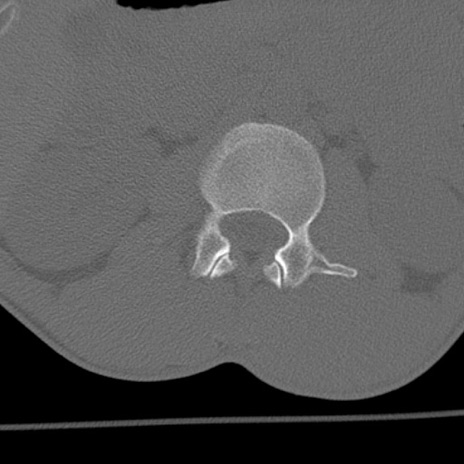

症例3 腰椎CT(横断像)

腰椎CT